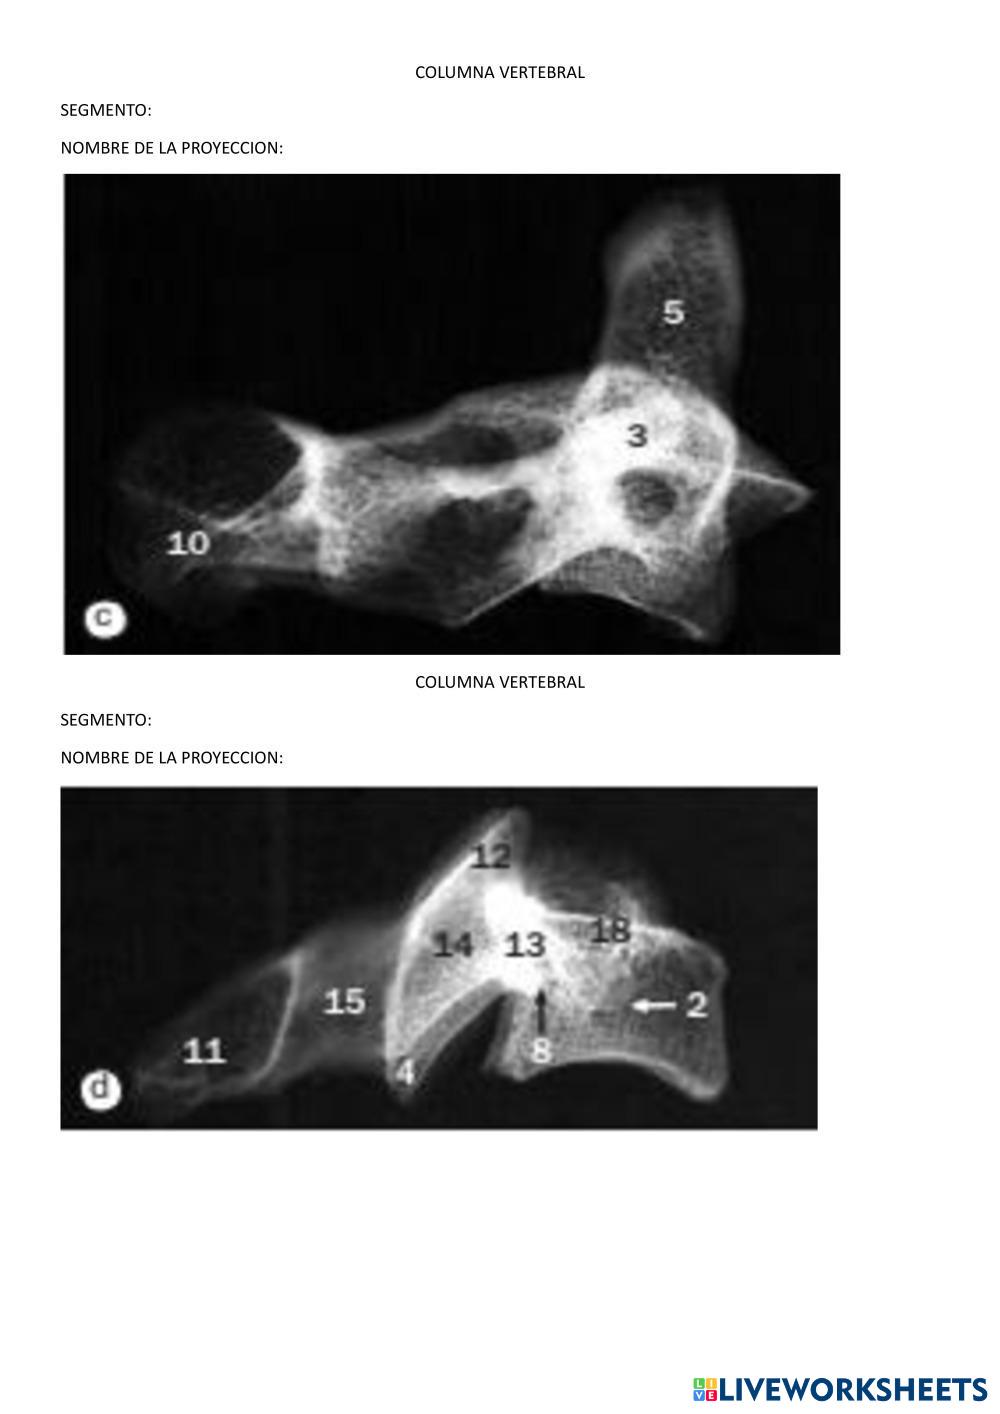

El cuerpo humano

El cuerpo humano